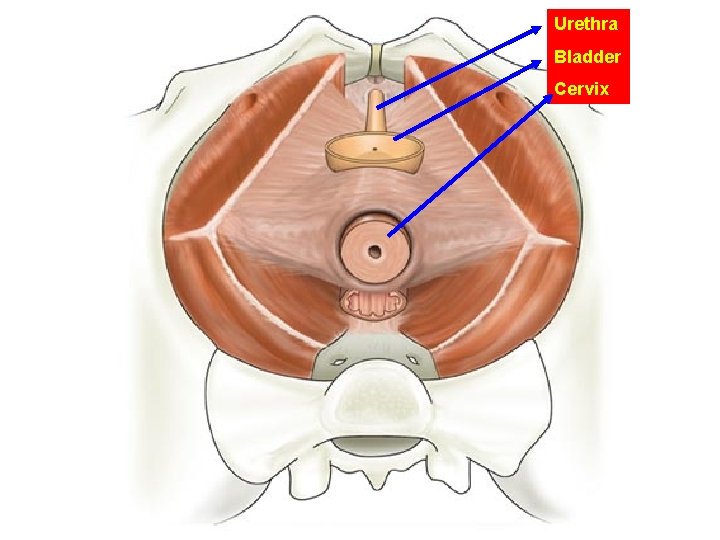

Urethra Bladder Cervix